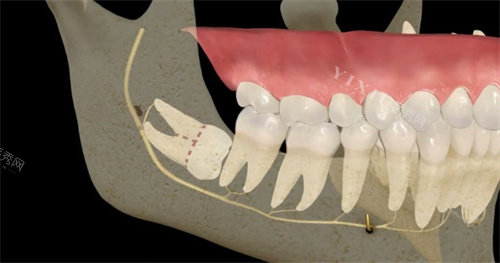

刚进诊所,前台小姐姐就注意到我捂着腮帮子的痛苦表情,赶紧递来冰袋让我冷敷,还优先给我安排了就诊。诊室里的氛围意外温馨,墙上贴着卡通版的牙齿科普漫画,牙椅旁边甚至放着个小玩偶,让我原本紧张到嗓子眼的心稍稍放下。接诊的赵医生拿着口镜检查时特别温柔,发现我的智齿是横着长的阻生齿,卡在牙槽骨里,难怪疼,他调出我的口腔 CT 影像,用手机上的 3D 模型给我演示拔牙过程,哪里需要切开牙龈、哪里要小心避开神经,讲得明明白白,还说会尽量减少创伤,术后修复更快。

拔牙前,护士小姐姐帮我量血压、测凝血功能,反复确认我没有过敏史,还贴心地给我披上小毯子。打麻药时,我攥紧了手心,赵医生却像哄小孩似的安慰我:“就像被蚂蚁叮一下,数到三就不疼啦!” 没想到真如他所说,麻药起效后,除了感觉牙齿被轻轻晃动,全程几乎没有痛感。赵医生手法特别稳,先用工具小心分离牙龈,再精细地把智齿分成小块取出,整个过程干净利落,还时不时问我有没有不舒服。原本以为至少要折腾半小时,结果不到 15 分钟就结束了,我甚至都没反应过来。